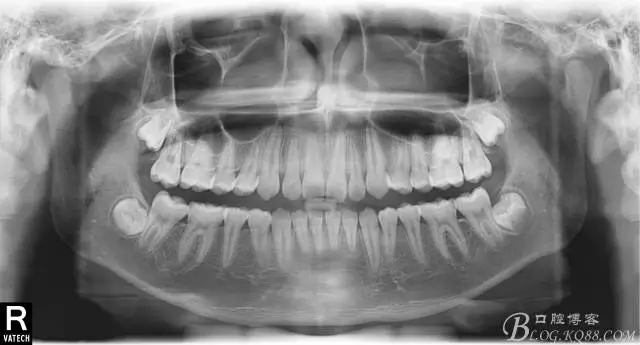

術后全景,側(cè)位照。